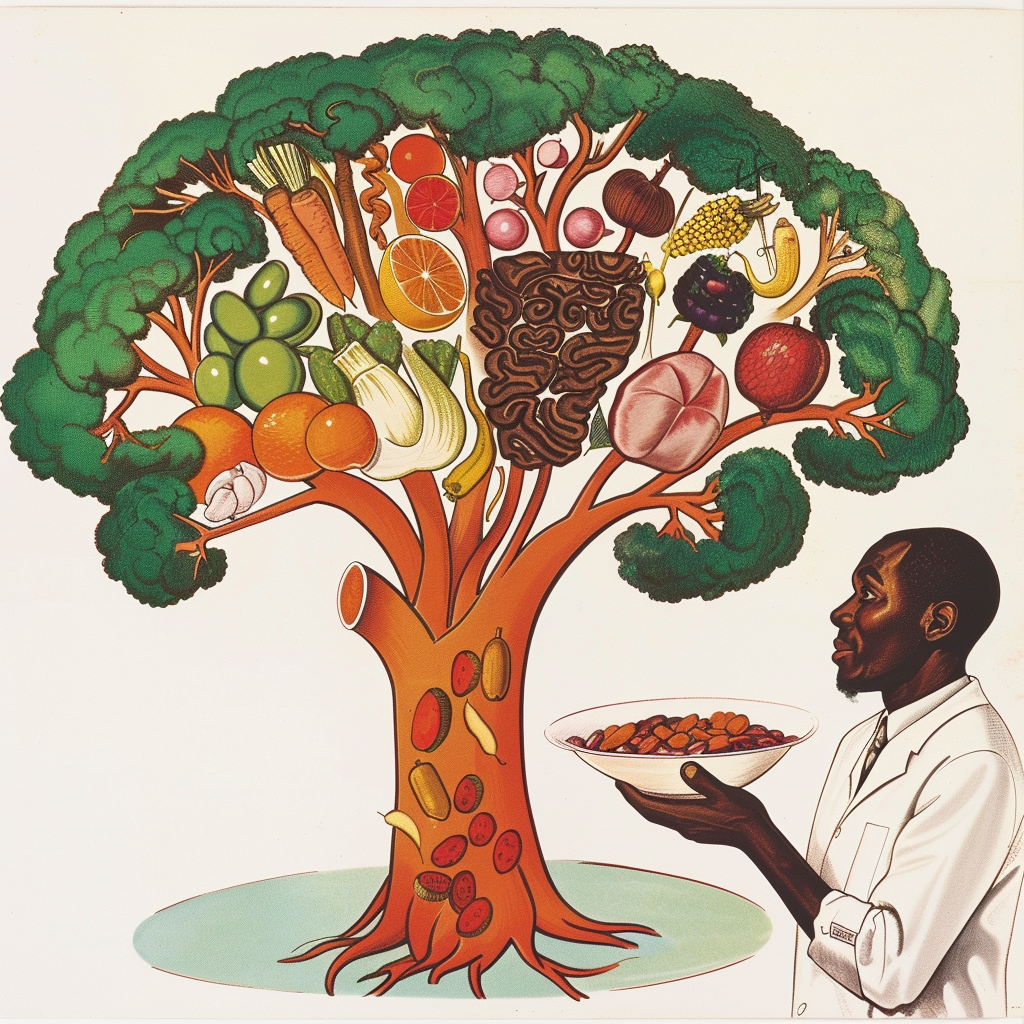

“dēverticulum“un (“arayolu, sapma”) alternatif bir telaffuzu olan “dīverticulum“dan türemiştir ve kendisi de “başka bir yöne dönmek, sapmak” anlamına gelen “dēvertō“den gelmektedir. Divertiküler hastalık, divertiküllerin (organ boşluklarında fıtığa benzeyen, balon benzeri,… Devamını oku